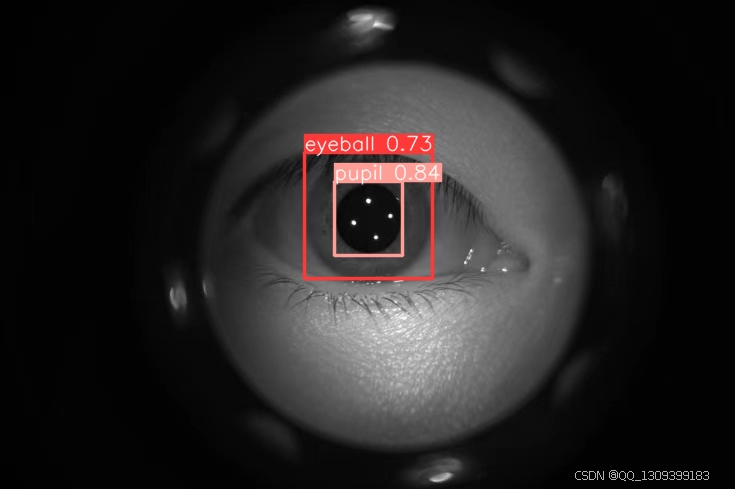

model = YOLO(r"best.pt")

model.predict(source=r"73.jpg",

save=True )

4. 直径计算

几何测量

一旦模型能够准确地定位瞳孔和眼球,就可以基于预测结果计算其直径。对于圆形物体来说,可以直接测量两个最远点之间的距离;对于非标准形状,则可能需要用椭圆拟合或者其他数学方法来估算。